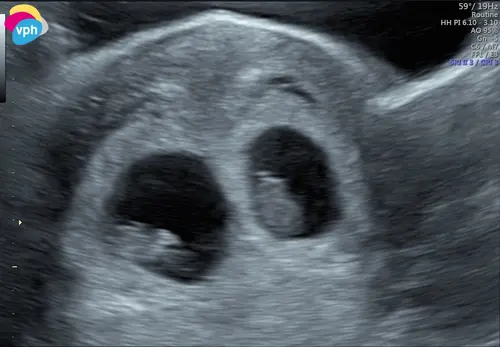

Hey! Heb ik ook gehad. de gehele zwangerschap bleef eentje kleiner + kleinere vruchtzak. Uiteindelijk kwamen ze bij mij erachter dat dit kwam doordat de kleinste maar 2 bloedvaten in zijn navelstreng had zitten. Uiteindelijk is alles goed gekomen. Hadden 1 kilo en 3cm verschil bij de geboorte. Nu 2 jaar later, 1,5 kilo en 5 cm馃槀

Ik vind het erg spannend. Het verschil in lengte is klein (1 dag) maar de zak van baby A was wel 2 a 3x zo groot als Baby B. Ik merkte dat de VK het zorgelijk vond.. poe! Ik vind het heftig. Fijn om te horen dat er positieve uitkomsten zijn